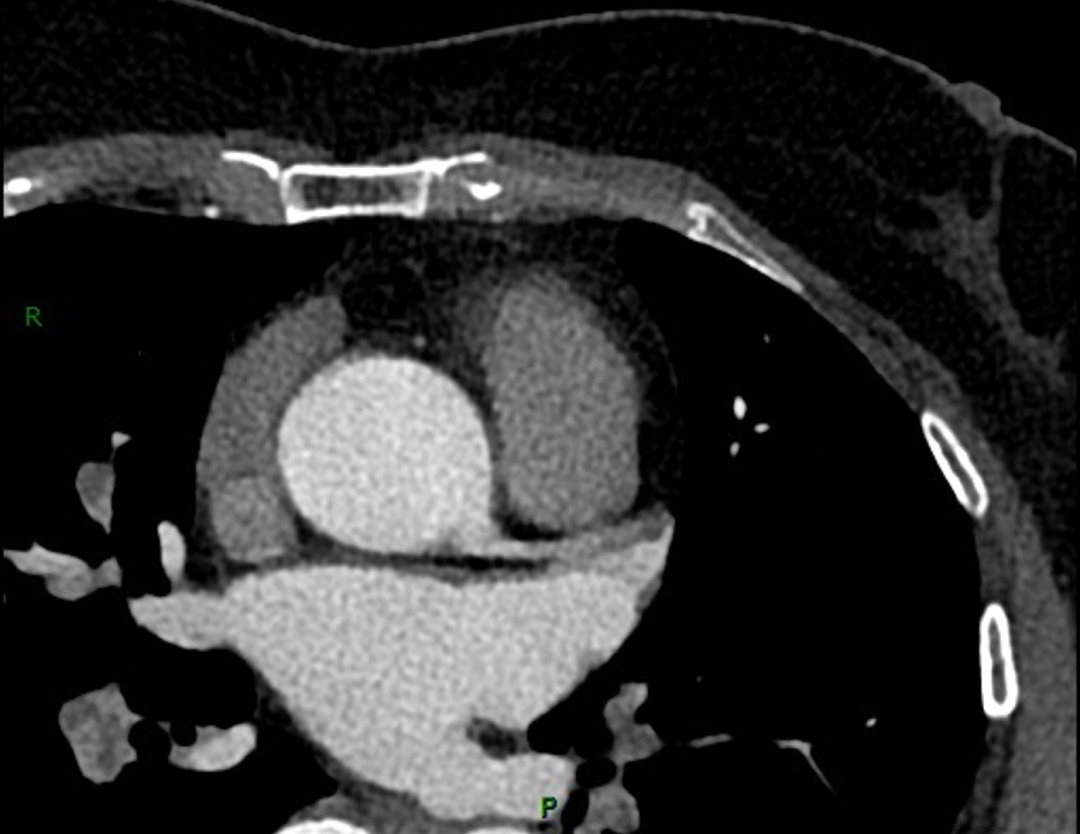

放射科副主任阚晓婧秉持精益求精、一丝不苟的阅片准则,在当日晚间细致复盘患者全部造影影像资料。常人极易忽略的细微血管异常,没有逃过她敏锐的双眼。在常规冠脉影像之外,她敏锐捕捉到患者肺动脉存在隐匿血栓病变,这一致命隐患极易被冠心病病史掩盖,一旦肺动脉完全栓塞,病情凶险、救治难度极大,随时会危及患者生命。

发现关键异常后,阚晓婧第一时间联合王佳佳主治医师,立刻致电联系患者家属,详细告知病情凶险程度,紧急提醒患者务必即刻住院接受规范诊疗,牢牢抓住黄金救治窗口期,避免血栓进展恶化、错过最佳治疗时机。正是这份不分昼夜的责任坚守、严谨缜密的临床判断,让潜藏的危重病灶早早暴露,让患者得以第一时间开展针对性治疗,规避了肺动脉完全闭塞的危重结局。

肺动脉栓塞发病隐匿、进展迅猛,致死率极高,极易被基础心脏疾病掩盖漏诊。多年来,阚晓婧始终深耕心血管影像诊断一线,坚守影像阅片第一道防线,以专业慧眼穿透病灶迷雾,以极致细心排查细微隐患。她始终坚持影像服务临床、细节守护生命,不遗漏任何一处微小异常、不放过任何一项潜在风险,日复一日在黑白影像里抽丝剥茧,用扎实专业功底、高度责任意识,为临床诊疗精准指路,为万千心血管患者筑牢健康第一道屏障。